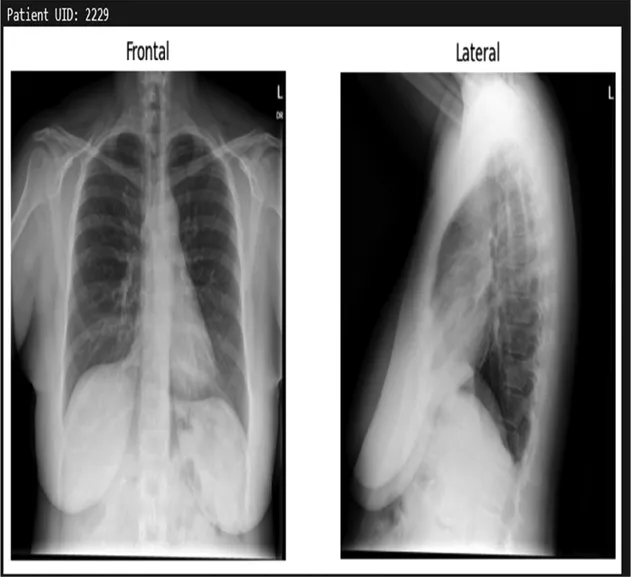

Training details

The dataset used in this study is the Indiana University Chest x-ray Dataset, which consists of 7,430 images of frontal and lateral chest x-rays belonging to 3,825 patients. Each image is paired with corresponding radiology reports that provide detailed findings regarding the patients' conditions. This dataset serves as the foundation for training the model to generate textual descriptions based on visual inputs.

Table 3. Example predictions of ChestX-transcribe.